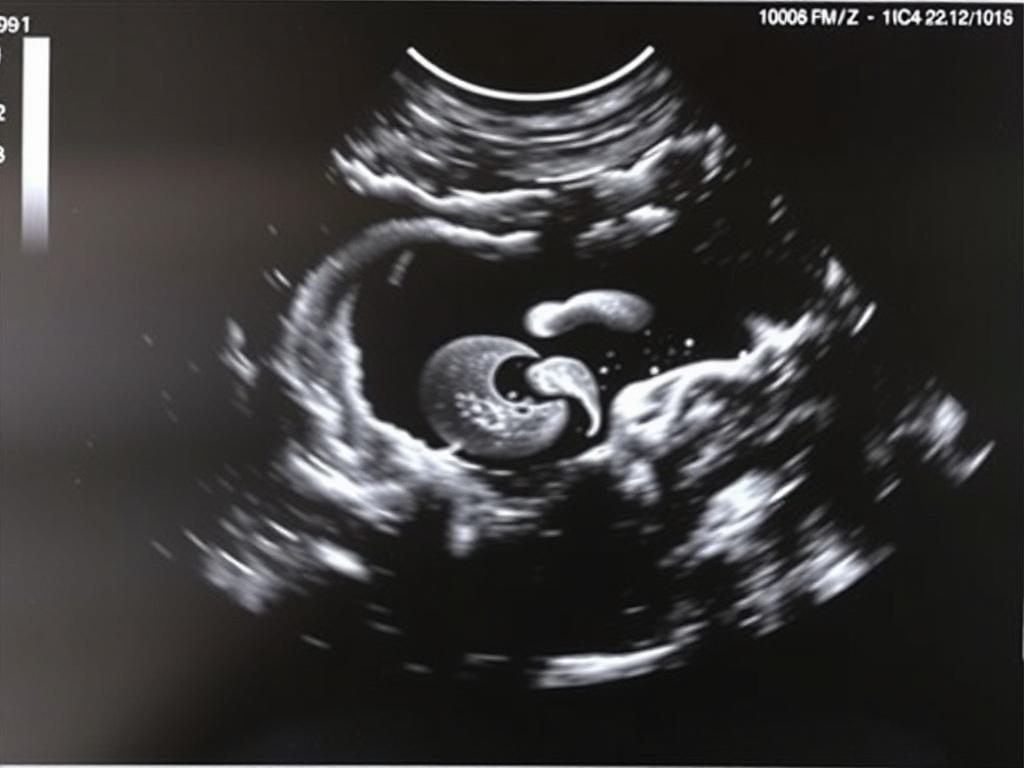

Abdomen, organes internes et système urinaire

L’inspection de l’abdomen inclut l’estomac, le foie apparent, les reins et la vessie. Les reins doivent apparaître présents et symétriques, la vessie se remplissant régulièrement, signe d’une fonction rénale active.

Un aspect dilaté des cavités rénales ou une absence apparente de vessie peut orienter vers un bilan complémentaire, parfois vers une IRM fœtale ou des contrôles échographiques rapprochés.

L’exploration suit un protocole méthodique. Le praticien balaie successivement le crâne, le cerveau, la face, le rachis, le cœur, l’abdomen, les reins, la vessie, le cordon et les membres, sans oublier la localisation du placenta et l’estimation du liquide amniotique.

Chaque site fait l’objet de mesures standardisées et d’une analyse qualitative : présence, symétrie, contours et vascularisation. Le compte rendu précise les mesures biométriques et signale tout élément inhabituel nécessitant un complément d’examen.